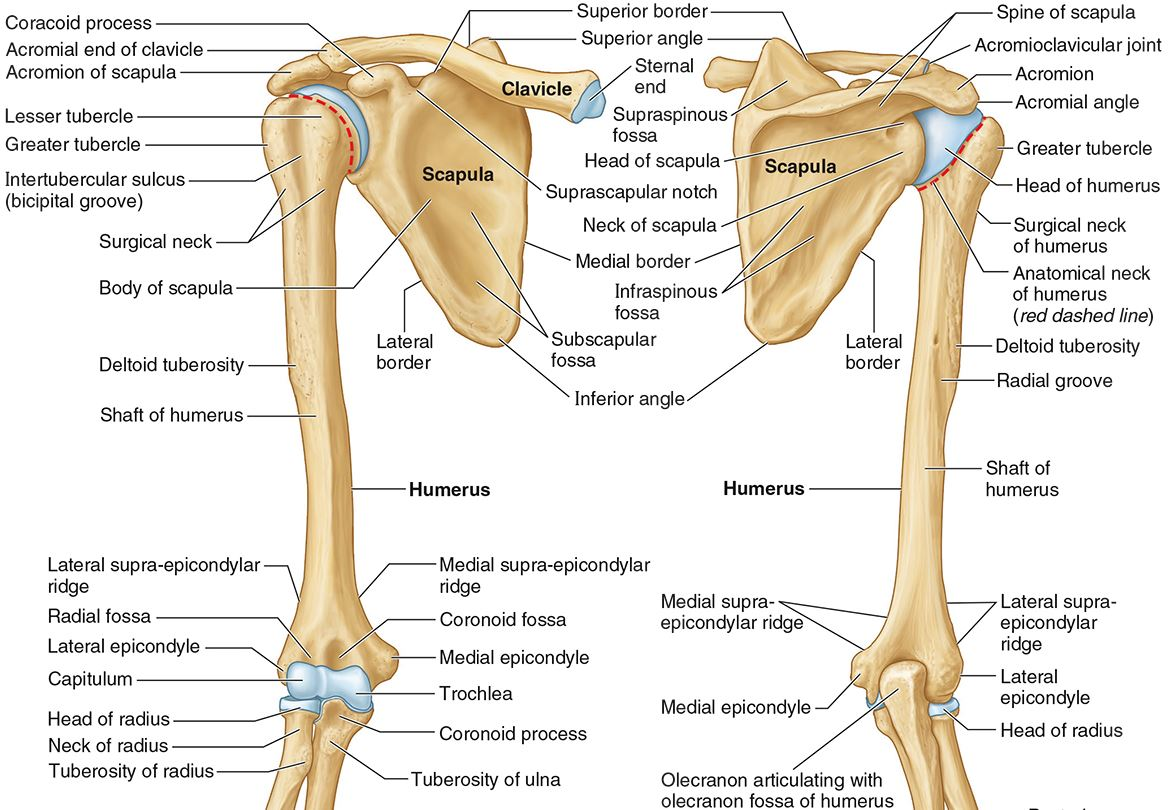

What is the only bone in the upper arm?

The humerus

What part of the humerus is this?

The head of the humerus articulates with the scapula at the glenohumeral joint.

What part of the humerus is this?

The anatomic neck is an indentation distal to the head and provides an attachment for the fibrous joint capsule of the glenohumeral joint.

What part of the humerus is this?

The greater tubercle lies lateral and distal to the anatomic neck.

What part of the humerus is this?

The lesser tubercle lies on the anterior/medial side of the humerus, just distal the anatomic neck.

What part of the humerus is this?

The intertubercular (bicipital) groove lies between the greater and lesser tubercles.

What part of the humerus is this?

The surgical neck is a narrow area distal to the tubercles. It is a common site for proximal humerus fractures.

What part of the humerus is this?

The humeral shaft features the deltoid tuberosity laterally for the distal insertion of the deltoid muscle.

What part of the humerus is this?

The radial groove is an oblique depression that contains the radial nerve and deep brachial artery.

Which parts of the humerus is this?

The medial and lateral epicondyles are distal prominences to which many forearm tendons attach, near the elbow joint.

Which parts of the humerus is this?

The medial and lateral supracondylar ridges extend superiorly from the medial and lateral epicondyles.

Which parts of the humerus is this?

The trochlea and the capitulum (the condyles) are the most distal surfaces of the humerus, where it articulates with the forearm bones at the elbow joint

What part of the humerus is this?

The olecranon fossa is a posterior depression above the trochlea that receives that olecranon process of the ulna

What part of the humerus is this?

The coronoid fossa is an anterior depression above the trochlea that receives that coronoid process of the ulna.